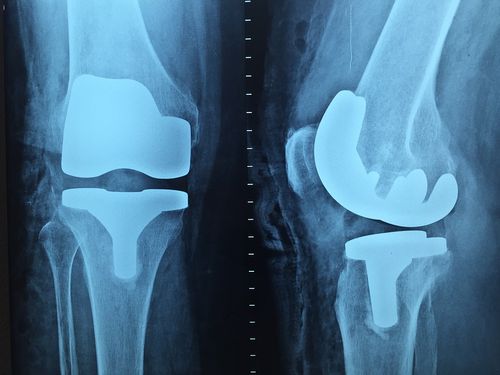

무릎 관절염 치료방법

무릎 관절염의 치료 방법은 다양합니다. 비수술적 치료로는 체중 감량, 물리치료, 약물 치료 등이 있습니다. 수술적 치료로는 관절경 수술, 관절 치환술, 관절 절제술 등이 있습니다. 치료 방법은 환자의 연령, 증상의 심각성, 관절 손상 정도 등을 고려하여 결정됩니다.

4. 수술 치료: 위 치료 방법이 효과가 없는 경우 수술이 필요할 수 있습니다. 수술은 관절경 수술, 관절 치환술, 관절 절제술 등이 있습니다.